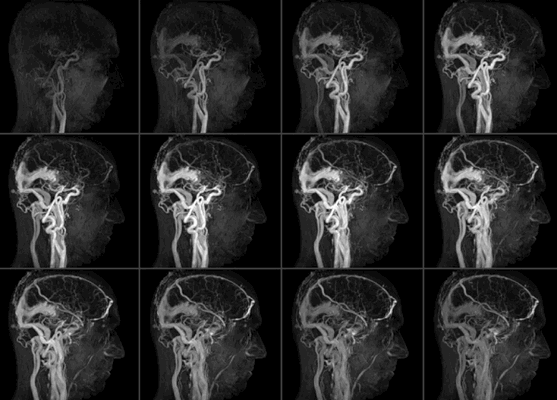

- МР-ангиография — высокоэффективный метод быстрой оценки кровотока в аорте и периферических артериях. Магнитно-резонансный томограф позволяет просматривать изображения сосудов в двухмерном и трехмерном режимах.

МР-ангиография — оценка проходимости кровотока, состояния даже мельчайших сосудов в двухмерном и трехмерном режимах.

Что показывает МР-ангиография сосудов

Магнитно-резонансная томография — это высокотехнологичное, информативное исследование. Его используют для визуализации мягких тканей, внутренних органов. Способ диагностики универсальный, есть несколько модификаций методики. Они позволяют решать конкретные задачи исследования. Ответ на вопрос, видны ли сосуды на МРТ, также положительный. Существует вариант обследования, которые позволяет визуализировать кровеносную систему на местном уровне.

Рисунок 1. МРТ сосудов головного мозга. Мешотчатая аневризма интраклиноидного отдела правой ВСА.

МРТ сосудов что показывает состояние вен, артерий, капилляров, проводится в рамках первичного обследования. Когда диагноза еще нет и его только предстоит поставить. Или для верификации, подтверждения ранее выявленных нарушений. Опровержения гипотез.

Рисунки 2,3. МРТ головного мозга. ОНМК по ишемическому типу в левой лобной доле. Очаговые изменения вещества головного мозга сосудистого характера.

МРТ сосудов действенно для диагностики заболеваний, скрининга патологических процессов в рамках профилактики и в случае, когда нужно изучить анатомические особенности тканей перед лечением и после него. Методика универсальная.